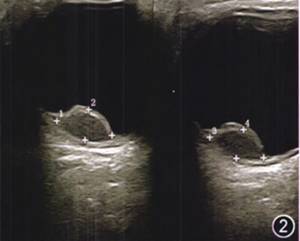

眼科检查:视力:右眼0.02,左眼1.0,眼压:右眼10 mmHg(1 mmHg=O.133 kPa),左眼14 mmHg,右眼前节未见明显异常,玻璃体混浊,视鼻上方可见一蘑菇样粉红色肿物,无色素,表面光滑,可见血管爬行,黄斑区中心凹反光不清(图1)。左眼未见明显异常。

图1 右眼视力下降患者右眼彩色眼底照相